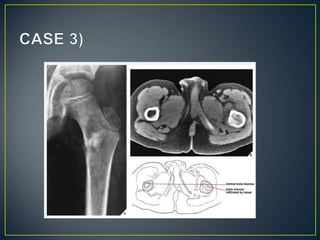

• Provide a precise evaluation of the extent of a bone

lesion .

• CT is moreover very helpful in delineating a bone tumor

having a complex anatomic structure.

• CT examination is crucial in determining the extent and

spread of a tumor in the bone if limb salvage is

contemplated, so that a safe margin of resection can be

planned .

• CT is also useful for monitoring the results of treatment.

• Evaluating the relationship between the tumor and the

surrounding soft tissues and neurovascular structures is

particularly important for planning limb-salvage surgery.

• MRI offers distinct advantages over CT.

• It has a few disadvantages as well.

• In the evaluation of intraosseous and extraosseous

extensions of a tumor, MRI is crucial because it can

determine with high accuracy the presence or absence of

soft-tissue invasion by a tumor .

• Assist in differentiation of intraarticular tumor extension

from joint effusion.

• Cant assess ossification and calcification.